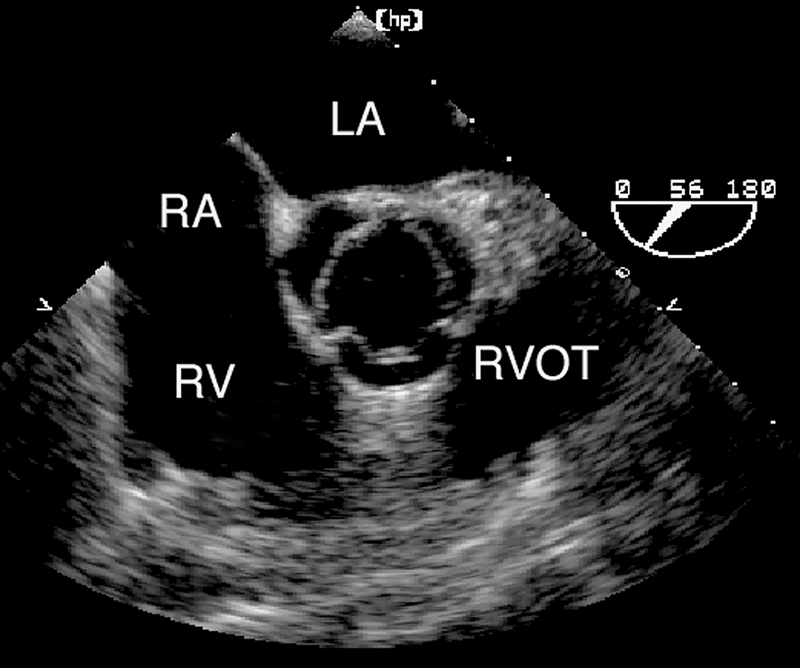

فحوصات تشخيصية لبعض امراض القلب والشرايين التاجية